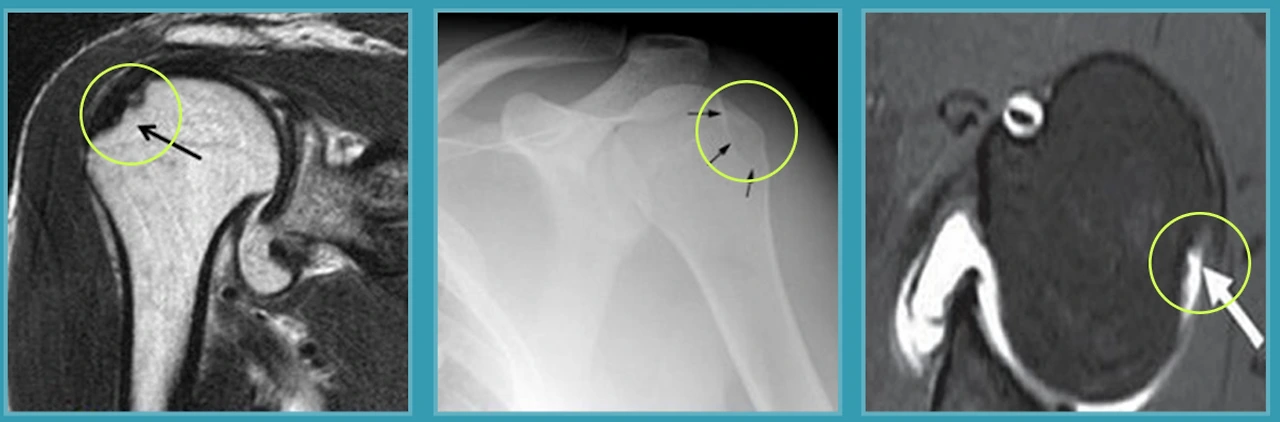

습관성어깨탈골의 진단과 치료

일단 환자와의 상담을 통해 습관성탈골인지를 파악하고 탈골되는 방향과 위치 등을 살핍니다. 그리고 X-ray, MRI, CT 등 검사장비로 정확한 어깨관절의 상태와 재발성 탈구여부를 확인하지요.

습관성어깨탈골의 원인으로는 방카르트병변과 힐삭스병변이 대표적입니다.

방카르트 병변

전영식 원장님 “어깨탈골과 함께 관절와순 손상 가운데 상완골두가 앞으로 빠지면서 전방의 관절와순이 동시에 손상되는 질환이 방카르트 병변입니다. 이 방카르트 병변은 습관성어깨탈골과 같이 재발성 탈골원인의 97% 정도를 차지할 정도이지요”라고 습관성탈골의 대부분은 방카르트 병변이라고 알려주시네요.

힐삭스 병변

어깨관절의 탈구로 인해 어깨관절과 맞닿는 상완골두 부분에 골결손이 생기는 것이 힐삭스 병변인데요. 방카르트 병변과 마찬가지로 외상으로 인해 어깨탈골이 발생하고 제 자리를 찾아가는 과정이 반복되면서 발생하며 잦은 어깨관절의 탈골과 상완골두 부위의 통증이 나타납니다.

전영식 원장님“안산 관절 척추 에이스병원에서는 방카르트 병변과 힐삭스 병변을 동시에 치료하는데요. 개별 환자의 상황에 맞춰 관절내시경을 통한 동시치료를 하는 것이지요”라고 설명하며 방카르트 복원을 할 때는 합병증과 재발요소를 제거한 완전한 수술인 중첩복원술을 하고, 힐삭스 병변을 효과적으로 제거하고 탈골의 재발을 방지하기 위해서는 Remplissage 술기로 탈골의 재발을 예방해야 한다고 알려주십니다.